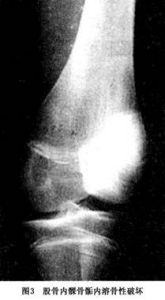

圖3 軟骨母細胞瘤1.肉眼所見腫瘤緻密而柔軟,與骨巨細胞瘤很相似或相同,與周圍骨的界限清楚,鈣化區似粗糙的濕木屑,顏色從灰到淺紅到棕色,有小的黃白色白堊樣區域,有時有纖維樣或軟骨樣外觀的白色區域,有時可見到出血和囊腔,可占據腫瘤的很大一部分。當腫瘤越過骨生長部,延及乾骺端時,可清楚地見到軟骨本身的破壞。腫瘤內可含有一些殘餘的軟骨,骨骺處的軟骨母細胞瘤可遠達關節軟骨,使關節軟骨薄而受壓。在罕見病例中,軟骨母細胞瘤可越過關節軟骨侵入關節內。

1.X線檢查 通常病變發生於長骨的骨骺內,呈圓形或橢圓形,直徑2~4cm低密度陰影 邊緣清晰,周圍有反應骨形成硬化緣,某些病灶可見點狀鈣化,相對應的骨幹可見連續的骨膜反應(圖1,2) 有時病變可伴有動脈瘤樣骨囊腫,X線片會顯示膨脹。成軟骨細胞瘤的X線表現的特點是在骨骺或骨性突起處有一位於中心或者偏心的溶骨性病變,其大小通常在5~6cm,病變界線清楚呈圓形或卵圓形。腫瘤周圍有一很細的硬化邊緣可將腫瘤與正常組織分開(圖1)。臨近的軟骨可以變薄或受到侵蝕。腫瘤可擴展至軟骨下骨,但很少進入關節間隙 有30%~50%的病例在病變中有鈣化灶。由於鈣化的程度不盡相同,有時需X線斷層或CT的幫助才能確定某些鈣化灶。約有30%的病例在鄰近的骨幹或乾骺端出現骨膜反應。軟組織出現包塊和並發病理性骨折者少見。